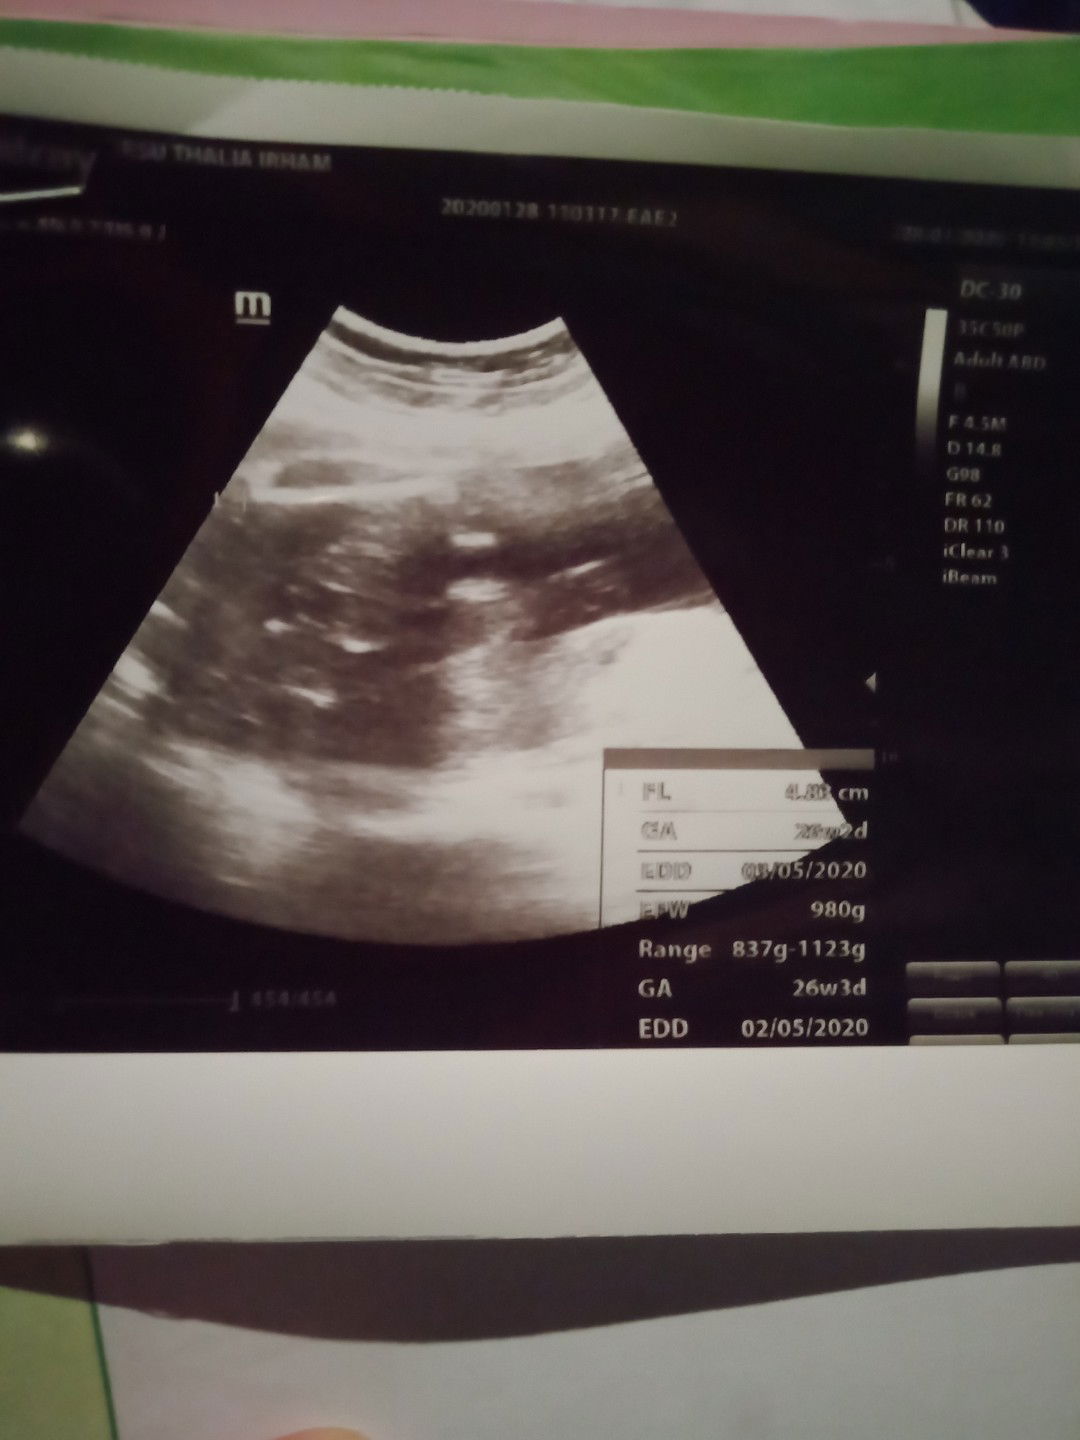

Halo moms, Yang HPL Akhir bulan April dan awal bulan mei gimana persiapannya? Aku baru beli sarung batik bumil dan tissue basah baby. Btw, aku mau cerita sedikit nih, kan minggu lalu aku sempat ke bidan krn sering banget sesak napas,pas di periksa kata bidan letak janin aku sungsang makanya tiap debay nendang pasti sesak,dan trus berat badan aku tiap bulan naik 5 kg dan kata bidan itu ga normal,dan trus DJJ nya katanya kecepetan 159 kilo/menit makanya bidan suruh usg nakutin banget sumpah? sempet mikirin yang ngga2 krn aku hamil anak pertama dari 2 tahun penantian. Selama seminggu ini aku sering sujud selama 20 menit setiap pagi,sianv,sore,malam. dan pas usg minggu depannya kata dokter debay aku sehat dan normal2 aja, kepala udah di bawah dan beratnya juga udah 980 g padahal baru 26W. Placentanya berada di fundus. Saat dengar kata dokter akhirnya kekhawatiran hilang. Udah lega rasanya abis USG.